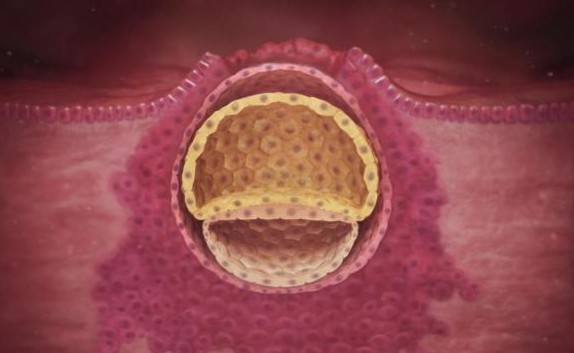

الأسبوع الرابع

هذا الأسبوع الذي يفترض أن يكون خلاله موعد الدورة الشهرية ومن اعراض بداية هذا الأسبوع انخفاض في درجة حرارة الجسم وتأخر الدورة الشهرية وهذا ما يجعل المرأة تلجأ لعمل اختبار الحمل للتأكد من وجود الحمل من عدمه.

خلال هذا الأسبوع تبدأ البويضة بالالتصاق بجدار الرحم ومن ثم تنقسم غلى قسمين أحدهما يبدأ الجنين بالتكون من خلاله وتكون أعضائه وأجهزته أما القسم الخارجي فيصبح بمثابة حماية للجنين وغطاء له كما تتكون منه المشيمة التي يتغذى عليها الجنين طوال فترة الحمل.